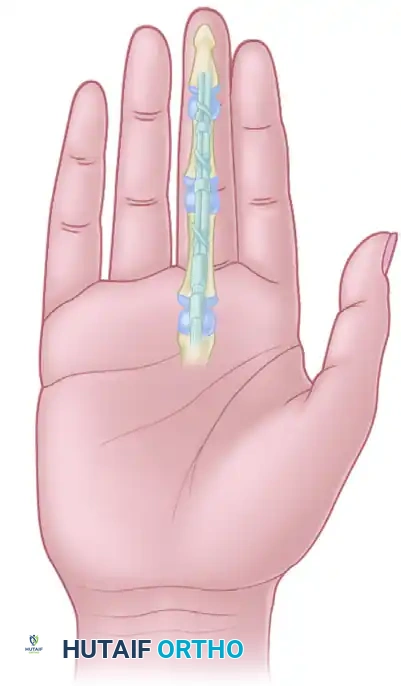

Figure 1: Illustration demonstrating a divided flexor digitorum profundus tendon near its insertion at the base of the distal phalanx.